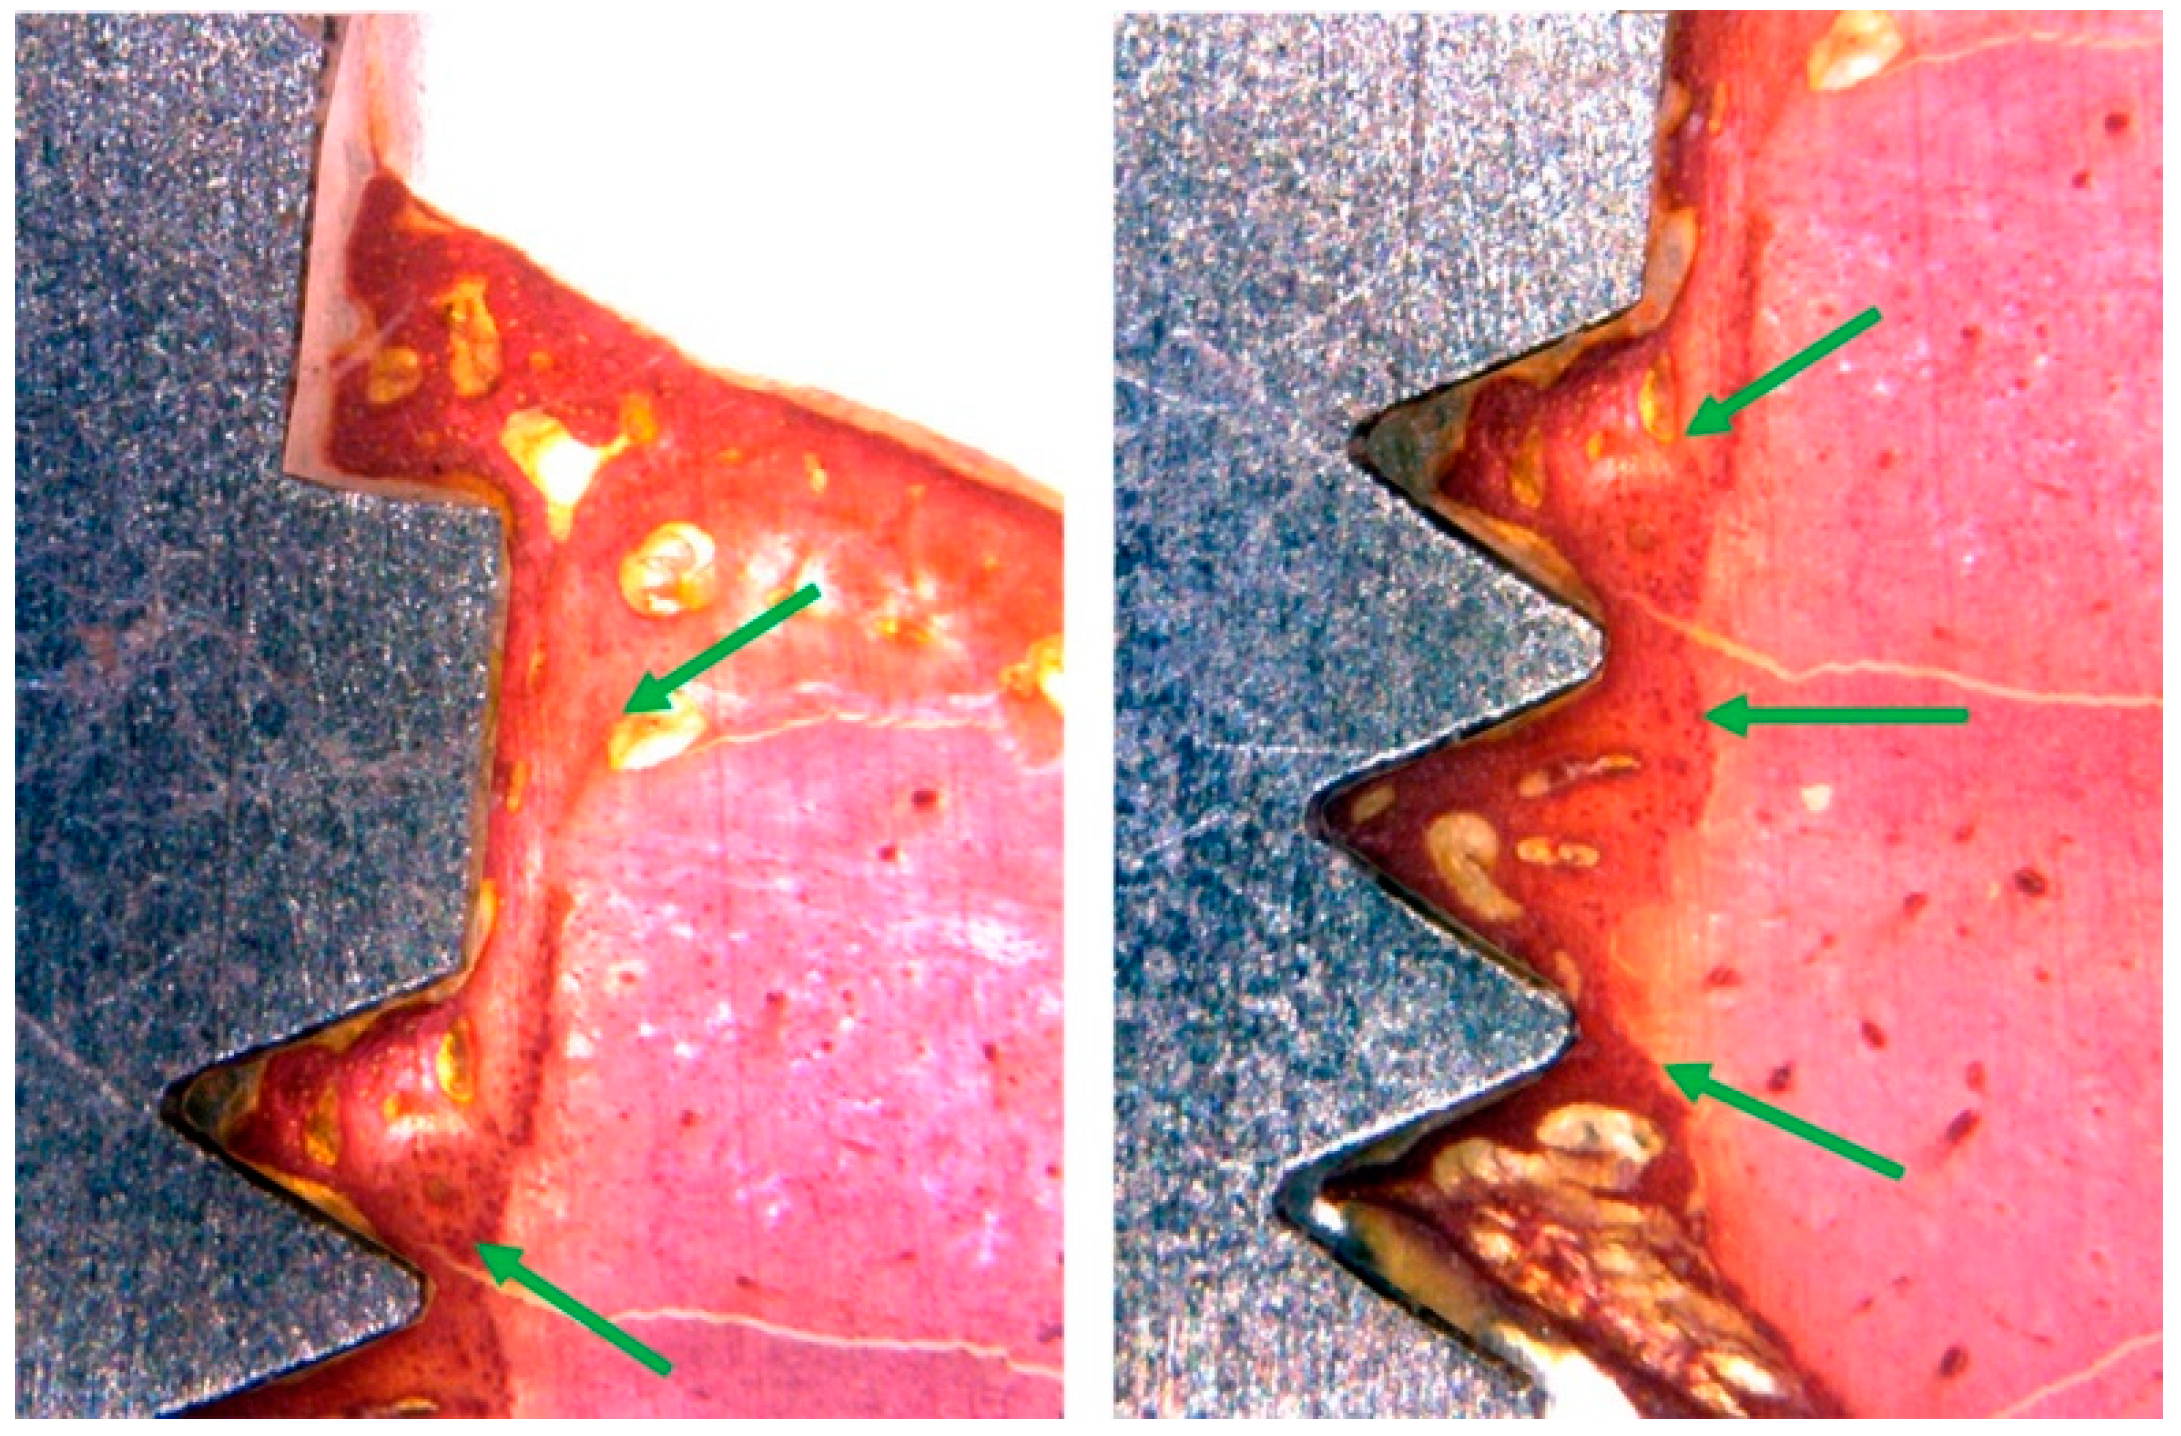

3.3. Histomorphological Analysis